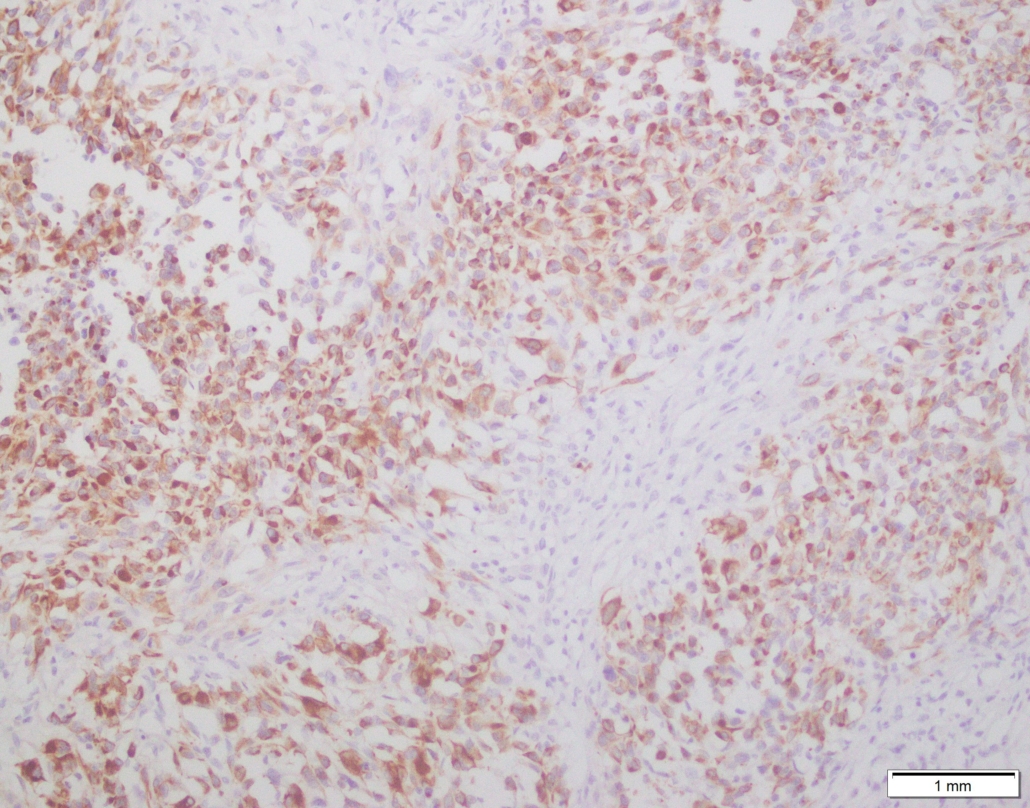

Case 03

Case presented by Dr Shaarif Bashir, FCPS (PAK), Shaukat Khanum Memorial Cancer Hospital and Reserach Centre, Pakistan